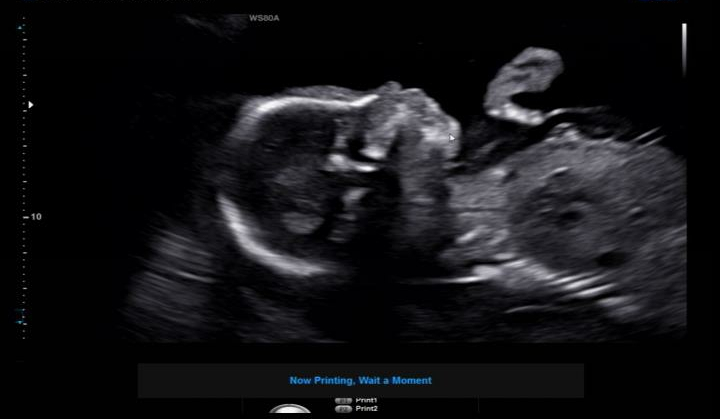

[임신25주-28주] 입체초음파/임신중독증검사/임신소양증

28주6일. 8개월차에 들어섰다! 그리고 드디어 기대하던 입체초음파 검사 날. 입체초음파 후기정말 많이 찾...